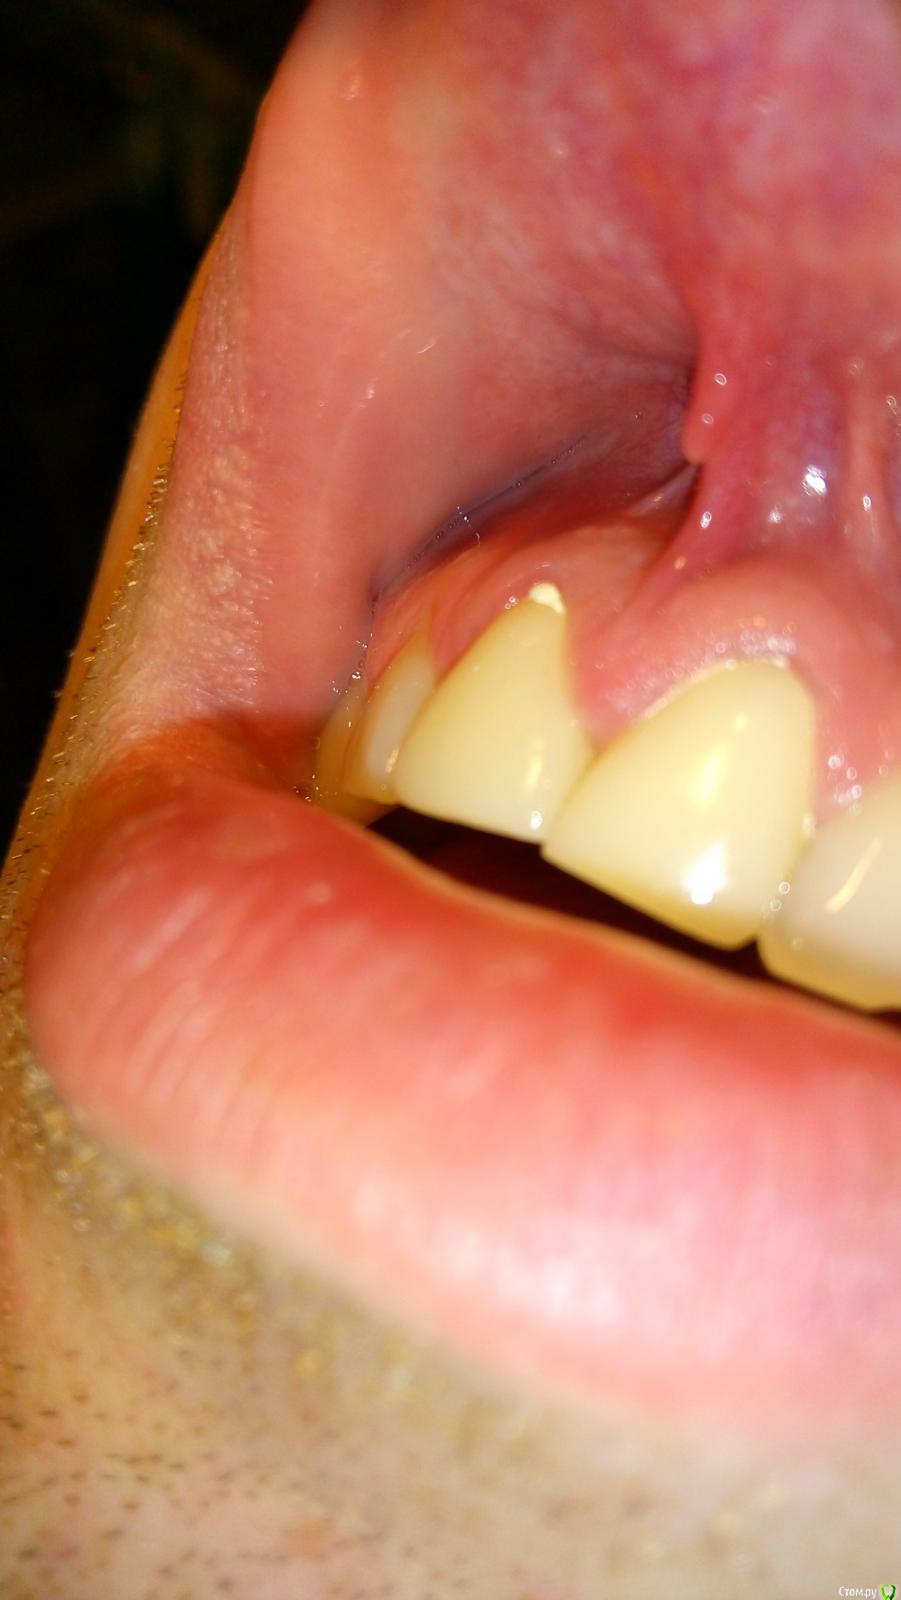

Opp80 Опубликовано 10 января, 2016 Автор Поделиться Опубликовано 10 января, 2016 (изменено) Чувствительность уменьшилась, но не прошла, далеко не прошла, пульсация периодическая и с отдачей в этот сосочек в периоды активного движения, т.е например поход в магазин, но не каждый раз (отметил на фото), у зуба есть небольшая подвижность так сказала другой врач на консультации, она сказала что возможно от того что врач постоянно лазил под десну, связки нарушаются, чтото типа того, но по симптоматике похоже на трещину, мой же врач на последней консультации, сказал может перфорация, и сказал делать ничего не будет больше, я же все мучаюсь, коронка поменяла свое положение появилась небольшая диастема за все время вмешательств.Прилагаю также понорамный снимок, и если кто глубоко заинтересуется КТ https://yadi.sk/d/TAjzSbIumYiyoP.S. когда попросил врача рентгены то он резко негативно высказался о том что я хочу спросить все на форуме, мол там не мастера, чему удивился чего бояться то, но снимки сказал даст, но они не понадобились я сделал КТ.Напомню, коронки стоят с 29 июля примерно, так и мучаюсь Изменено 10 января, 2016 пользователем Opp80 Ссылка на комментарий

Opp80 Опубликовано 10 января, 2016 Автор Поделиться Опубликовано 10 января, 2016 (изменено) Это снимок от 3 декабря (месяц назад) перед тем как врач будет до костной ткани все пробовать прочищать зондом, как понял так было, тут я немного боком сфотографировал диастема была уже но субъективно меньше Изменено 10 января, 2016 пользователем Opp80 Ссылка на комментарий

Opp80 Опубликовано 16 января, 2016 Автор Поделиться Опубликовано 16 января, 2016 (изменено) Уважаемые врачи посмотрите пожалуйста такие десна были до установок постоянок (фото 1,2) и после 3,4Это с коронками чтото нето? Изменено 16 января, 2016 пользователем Opp80 Ссылка на комментарий